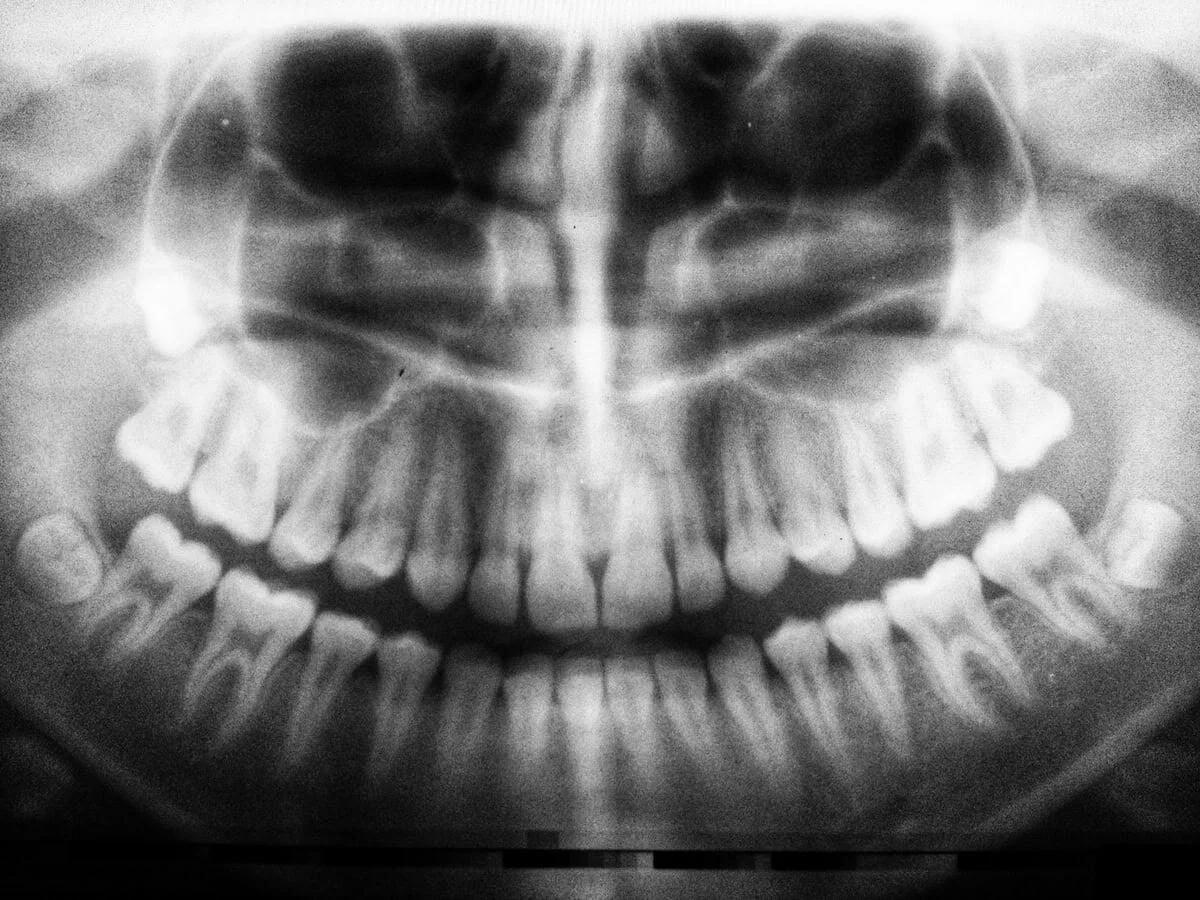

Digital xrays are an important part of a dental exam. They show the dentist many things that cannot be seen by the naked eye such as decay, infection, and fractures. Digital x-rays develop very quickly and give off 70% less radiation compared to conventional x-rays.